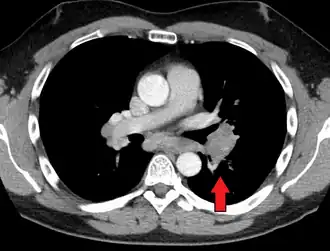

-

Hilar adenopathy especially on the person's left (coronal CT) -

Hilar adenopathy especially on the person's left (transverse CT)